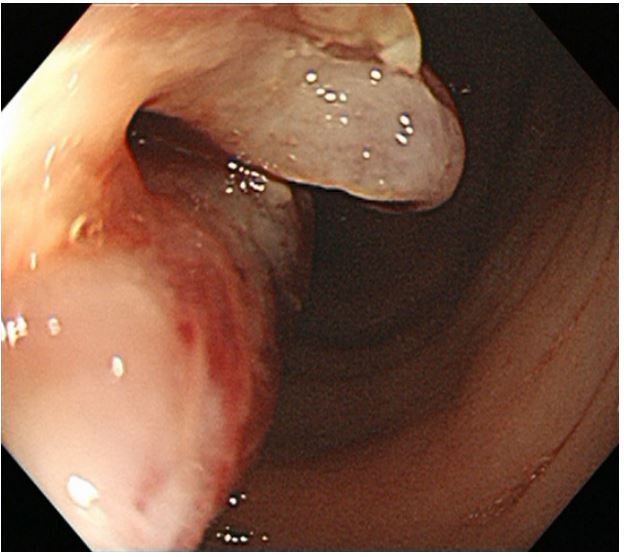

An eighty-year-old woman presented with the symptoms of abdominal pain, slight fever of 37-38°C, and body weight loss. Upper Gastrointestinal (GI) examination performed one month prior to presentation revealed a gastric tumor, while Esophagogastroduodenoscopy (EGD) showed a type 3 tumor in the gastric fundus and corpus (Figure 1a). However, food residues covering the tumor surface prevented precise observation. Colonoscopy revealed an irregular surface elevation in the splenic flexure of the colon (Figure 1b), in which an adenocarcinoma was detected by biopsy. Contrast-enhanced computed tomography (eCT) revealed advanced GC with extensive invasion of the transverse colon, spleen, and pancreas (Figure 2a,b). Peritoneal dissemination and lymph node metastasis were suspected. The eCT image also showed gas in the pancreatic duct, indicating fistulation from the stomach to the pancreatic duct due to tumor invasion (Figure 2b). This fistula was presumed to be the cause of the patient’s low-grade fever. Thus, relatively rapid surgery was performed to control bacterial infection of the pancreatic duct and ensure resection of the advanced GC. Open surgery was performed, and extensive invasion of the GC into the pancreas and transverse to the descending colon was detected. Fortunately, no obvious peritoneal dissemination was observed. Therefore, a total gastrectomy with D2 lymphadenectomy combined with distal pancreatectomy, partial colectomy, and cholecystectomy was performed. Cholecystectomy was added as it is performed along with total gastrectomy as the standard procedure in our institute. The resected gastric tumor measured 160×80 mm (Figure 3a). Pathological tests revealed a poorly differentiated adenocarcinoma of the stomach invading the pancreas, transverse colon, and splenic serosa (Figure 3b-e). No metastasis was identified in the dissected lymph nodes or peritoneum. The pathological cancer stage was IIIA, according to both the TNM Classification of Malignant Tumours-8th edition [13] and the 15th edition of the Japanese Classification of Gastric Carcinoma[14]. Approximately two months after surgery, we initiated adjuvant chemotherapy with tegafur/gimeracil/oteracil, which was discontinued after only two months due to severe adverse events. Two years after surgery, the patient remains alive without relapse.

Figure 1a: EGD showing a large type 3 tumor in the fundus and corpus of the stomach. The surface of the tumor was largely covered with food residue which prevented detailed observation.

Figure 1b: Colonoscopy showing an irregular surfaced elevation in the splenic flexure of the colon.